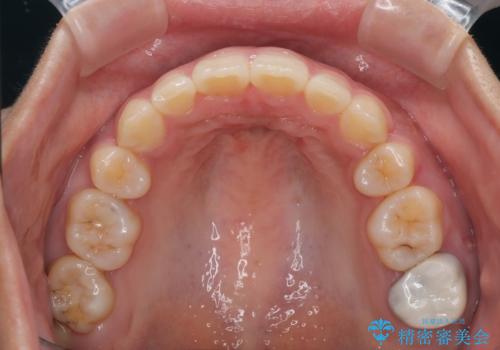

- 前歯のデコボコと口元の突出感を気にして来院された患者様です。

上下前歯がくちばしのように突出していたため、上下左右の第一小臼歯4本を抜歯し、ワイヤー装置にて矯正治療を行うこととしました。